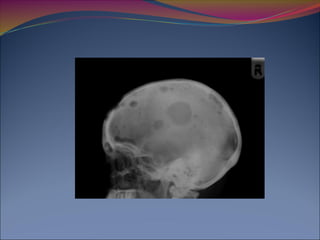

14 Rayos X:

Cráneo (AP y Lat)

80% de los pacientes tienen alteraciones en las Rx

Blood. 2011 May 5;117(18):4701-5.

14 Rayos X: Cráneo(AP y Lat) Columna Cervical (AP y Lat) Columna Torácica (AP y Lat) Columna Lumbar (AP y Lat) Fémur (AP y Lat) Húmero (AP y Lat) Tórax (PA) Pelvis (PA) 80% de los pacientes tienen alteraciones en las Rx Blood. 2011 May 5;117(18):4701-5.